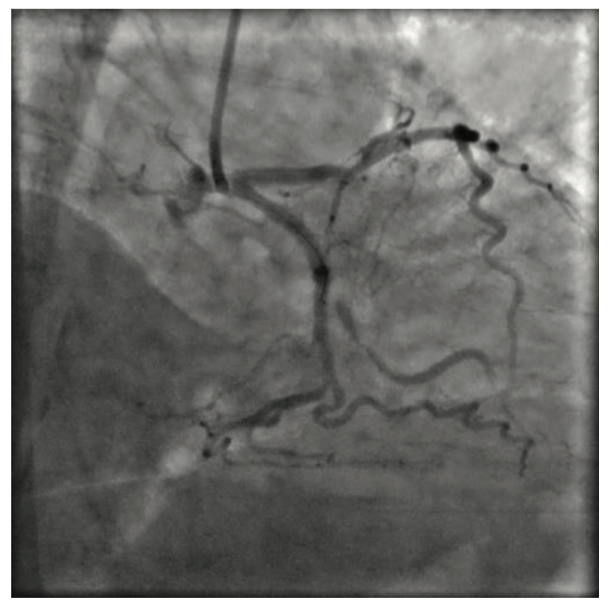

Whole blood viscosity has been shown to be reduced by contrast media injection.2 Although water’s viscosity is Newtonian (it stays constant under different flow conditions), blood’s viscosity follows non-Newtonian hydrodynamics as it increases under lower flow states (Figure 3). This is due to the interaction between RBC and plasma proteins that leads to chains of several RBC in series, ie, rouleaux formation in low flow states, a phenomenon that is clinically utilized in measurement of erythrocyte sedimentation rate. Since the flow markedly reduces distal to the subtotal occlusion, the viscosity distal to the stenotic lesion increases due to rouleaux formation by blood cells. The diameter of the capillaries is 8 to 10 microns, almost identical to that of RBC, so in normal flow conditions, RBC can only move through normal capillaries in single file. By injecting contrast media, the column of RBC is replaced by a lower viscosity medium. Advancing a hydrophilic wire at the same time utilizes the hydro planar surfing properties of the wire, so the wire finds the flow by itself and crosses the lesion. Whether the main reason for crossing the lesion was the reduced viscosity as compared to the surfing capacity of a hydrophilic wire is beyond the scope of this case report. The hydrophilic properties of the wire did not change during the procedure and the wire failed to cross the lesion by itself until we injected contrast medium forcefully, indicating that the viscosity reduction plays an essential role.

Whole blood not only has much higher viscosity than water at rest, but its viscosity is also inversely related to the flow due to its non-Newtonian nature. Because of the high degree of interaction between the elements of blood (RBC, white blood cells, and plasma proteins) when it is not flowing, a driving pressure significantly greater than zero is required for stationary blood to start flowing again. This is referred to as the yield stress required to initiate flow (Figure 3). During critical coronary stenosis, exhaustion of autoregulatory vasodilation of arterioles leads to capillary derecruitment, which further increases the resistance through the microcirculatory bed. This driving pressure, or required yield stress, is likely higher in severe coronary stenosis, and apparently can be overcome by injecting contrast media with increased force manually, as in our case.